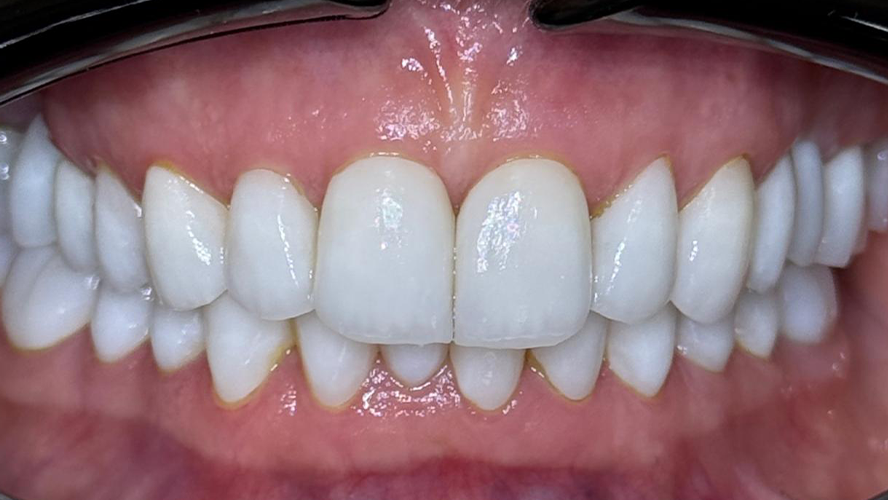

Kompleksowa odbudowa zgryzu

Kompleksowa odbudowa zgryzu łącząca leczenie ortodontyczne, fizjoterapeutyczne, implantologiczne oraz protetyczne pod postacią koron i licówek ceramicznych.